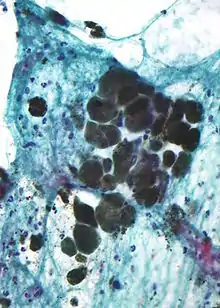

Microscopic appearance

Melanin is brown, non-refractile, and finely granular with individual granules having a diameter of less than 800 nanometers. This differentiates melanin from common blood breakdown pigments, which are larger, chunky, and refractile, and range in color from green to yellow or red-brown. In heavily pigmented lesions, dense aggregates of melanin can obscure histologic detail. A dilute solution of potassium permanganate is an effective melanin bleach.[54]